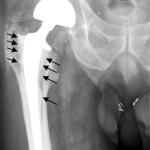

joint replacement

There is no doubt that replacing a hip or knee crippled by arthritis can vastly improve one's quality of life and u